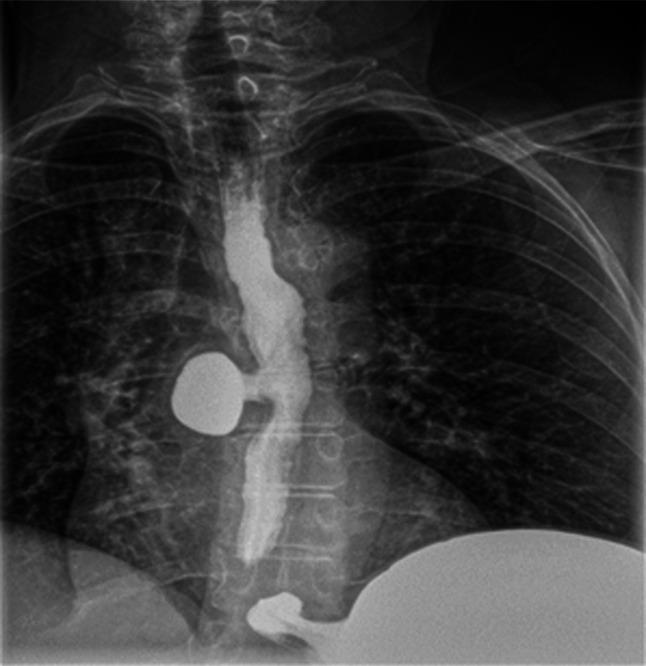

Esophageal diverticulum (ED) is a rare condition with a clinical presentation that can be variable. Esophageal diverticulum has been associated with motility disorders; however, the association with mid-ED is less clear. Hypercontractile esophagus, also known as jackhammer esophagus, is a rare motility disorder of peristalsis diagnosed by esophageal high-resolution manometry after exclusion of mechanical obstruction. We describe the second reported case of mid-ED secondary to hypercontractile esophagus successfully treated through robotic diverticulectomy with long myotomy. KEYWORDS: esophagus; esophageal manometry; motility; diverticular disease.

食管憩室(ED)是一种罕见疾病,临床表现多变。食管憩室与动力障碍有关;然而,与中段食管憩室的关联尚不清楚。高收缩性食管,也称为风钻食管,是一种罕见的蠕动动力障碍,在排除机械性梗阻后通过食管高分辨率测压诊断。我们描述了第二例因高收缩性食管继发中段食管憩室的病例,该病例通过机器人憩室切除术加延长肌切开术成功治疗。关键词:食管;食管测压;动力;憩室病